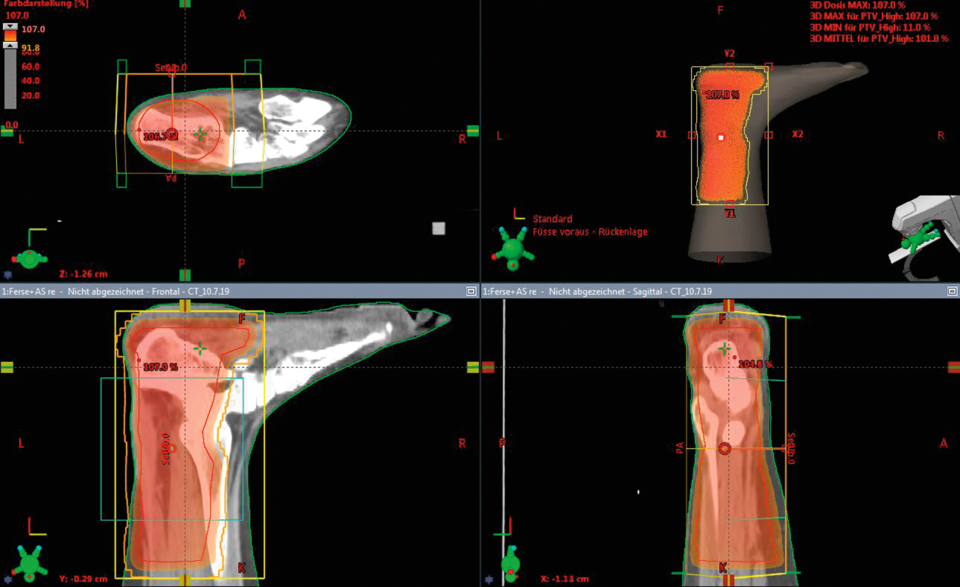

Mittels CT wird die Bestrahlung eines Patienten mit Achillodynie und Fersensporn geplant. Mittels CT wird die Bestrahlung eines Patienten mit Achillodynie und Fersensporn geplant. © Schneider T, Schneider­ K. internistische praxis 2019; 61: 284-300 © Medien­gruppe Oberfranken - Fachverlage GmbH & Co. KG, Kulmbach